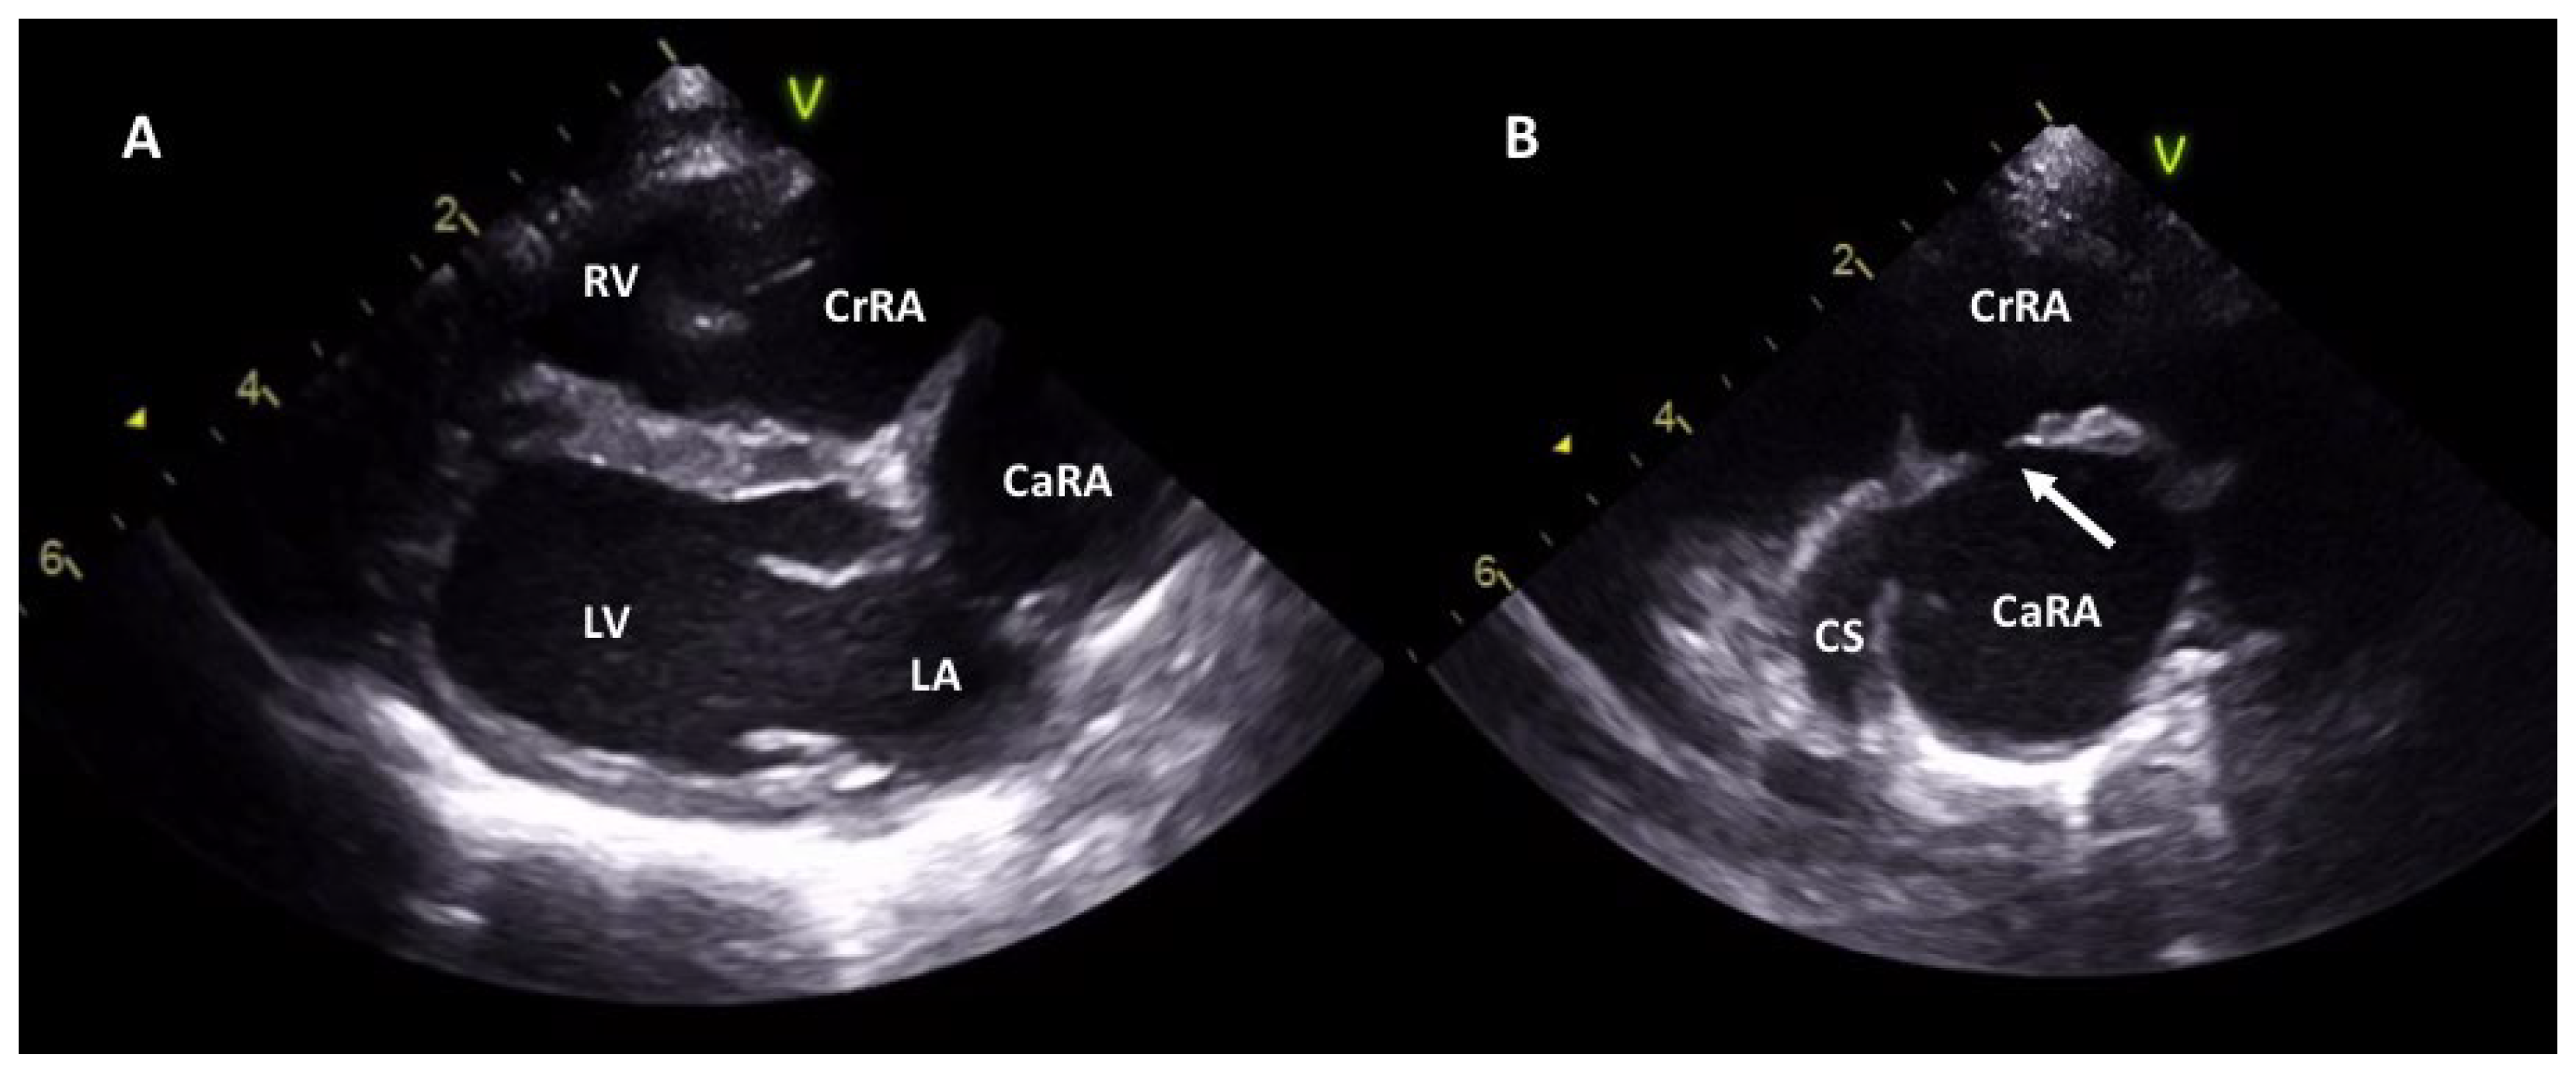

2.1. Case 1

2.2. Case 2